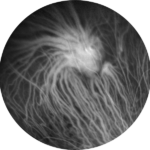

Figura 6. Ecografia Bscan all’occhio sinistro.